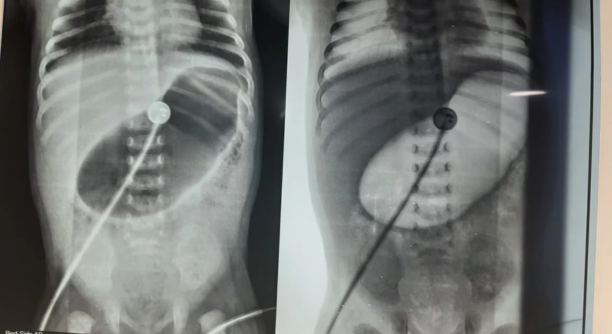

Ultrasound Abdomen: Large heterogeneous mass with cystic and solid components

CT Scan: Well-defined retroperitoneal mass measuring 8×6 cm, displacing adjacent bowel loops

Procedure: Elective exploratory laparotomy under general anesthesia

Findings: Large encapsulated mass arising from the retroperitoneum, adherent to adjacent mesentery but not involving major vessels

Surgery: Complete excision of the tumor without spillage